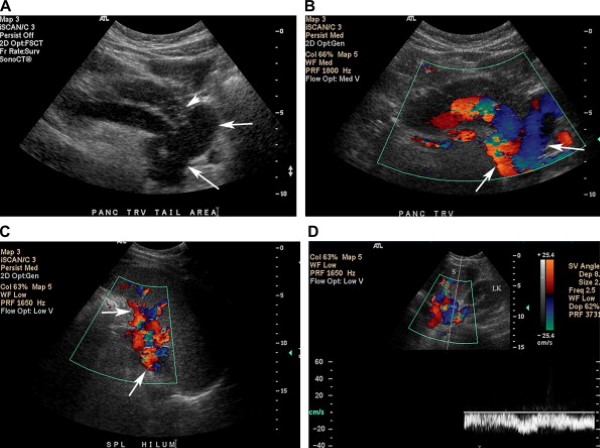

Giãn tĩnh mạch lách-thận

Các nối tắt tĩnh mạch lách-thận và dạ dày-thận có thể nhìn thấy bằng siêu âm dưới dạng các tĩnh mạch ngoằn ngoèo nằm bên trong rốn lách và hố thận, nhìn rõ qua mạn sườn trái dùng lách làm của sổ âm [2]. Các tĩnh mạch nối tắt từ dạ dày hoặc lách giãn to, đổ vào tĩnh mạch thận trái (Hình 14).

Hình 14. Giãn tĩnh mạch lách – thận ở sản phụ 23 tuổi có tiền sử u carcinoid ruột thừa. Bệnh nhân có tiền sử huyết khối tĩnh mạch cửa sau khi phát triển di căn gan. (Hình A) Ảnh thang xám cắt ngang vùng tuỵ phát hiện các mạch máu ngoằn ngoèo (các mũi tên) gần đuôi tuỵ (đầu mũi tên). (Hình B) Ảnh siêu âm màu vùng đuôi tụy cho thấy các tĩnh mạch giãn ngoằn ngoèo các (mũi tên). (Hình C) Nhiều mạch máu giãn ở vùng rốn lách (gọi là búi tĩnh mạch, varices). (Hình D) Tĩnh mạch nối tắt giữa lách (S) và thận trái (LK) có phổ tĩnh mạch cửa.